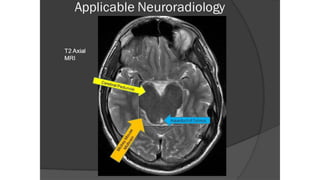

T2 sequence- Flip side of T1

•T2

• CSF, AQ/VT HUMOR WHITE

•Fat black/white mater

•Water white

•Blood vessel dark

•CSF study

•Lesions in brain